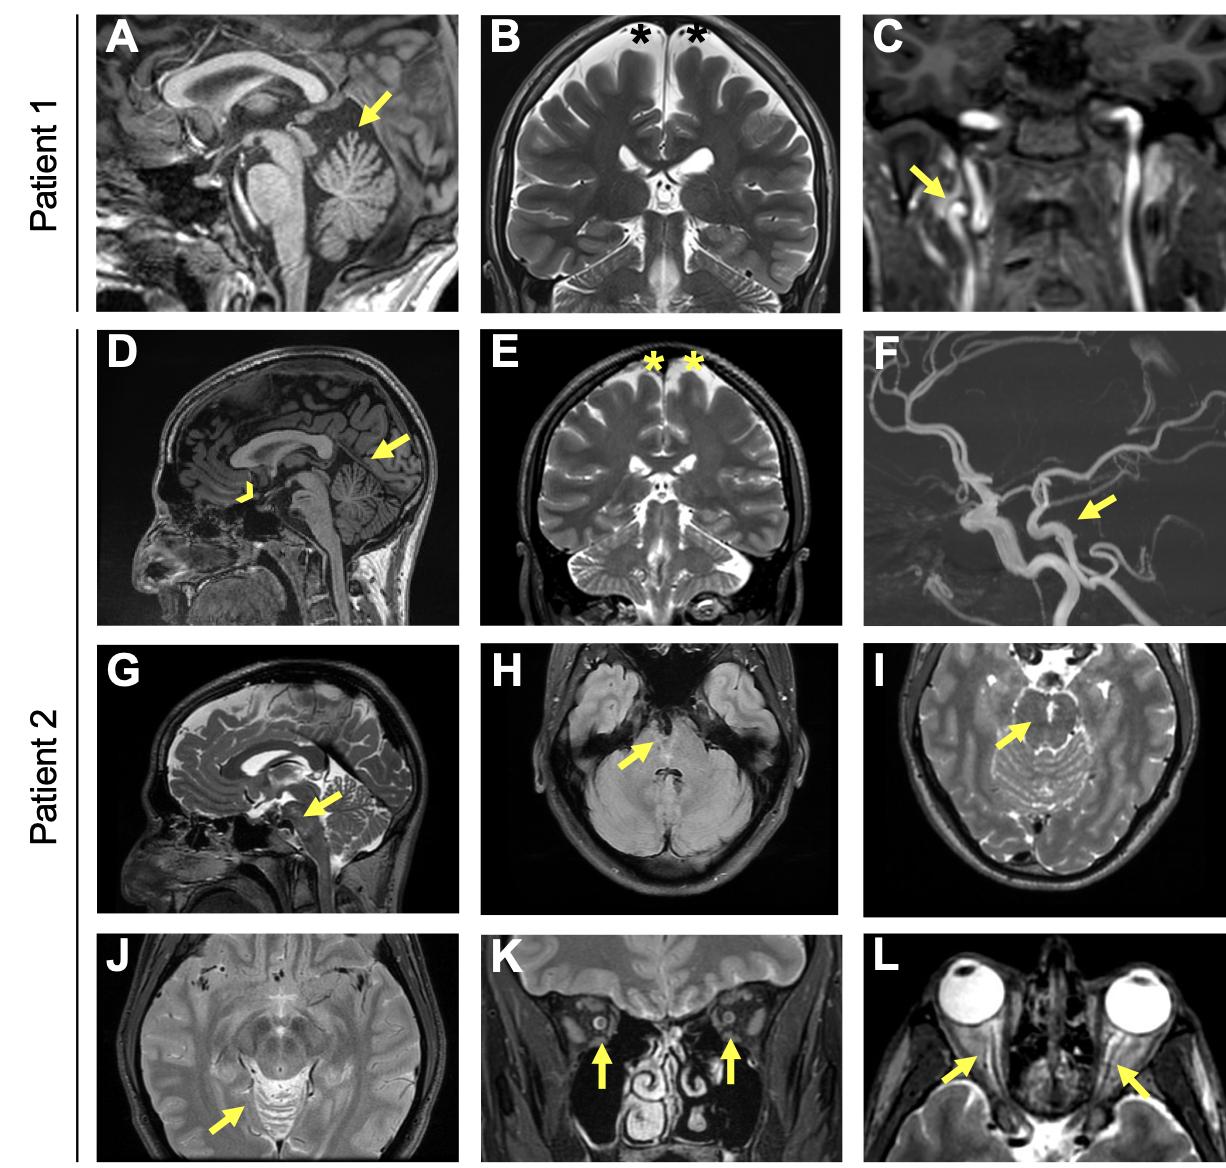

Supplemental Figure 2. Cerebral MRI of Patients 1 and 2. A) Sagittal T1 weighted MRI images showing cerebellar atrophy involving specifically the superior part of the cerebellar vermis (arrow). The pituitary gland is normal both for the anterior and the posterior part. B) Coronal T2 weighted images showing diffuse widened subarachnoid spaces suggesting mild cerebral atrophy (black asterisks). C) Coronal T1 weighted imaging showing loop of the cervical segment of the right internal carotid artery, which is an unusual finding in young adults (arrow). D) Sagittal T1-weighted images showing cerebellar atrophy involving specifically the superior part of the cerebellar vermis (arrow). The pituitary gland is normal both for the anterior and the posterior part (arrowhead). E) Coronal T2 weighted images showing diffuse widened subarachnoid spaces suggesting mild cerebral atrophy (asterisks). F) 3D Time of Flight images showing the dolichoectasia of the basilar artery (arrow). G) Sagittal T2 weighted images showing the slight brainstem compression (arrow). H) Axial Fluid Attenuated Inversion Recovery T2 weighted images showing the dolichoectasic basilar trunk in a mid- pons cleft (arrow). I) Axial T2 weighted images showing stretched enlarged perivascular spaces in the mid-pons (arrow). J) Axial T2 weighted images showing the atrophic superior vermis (arrow). Coronal (K) and axial (L) T2 weighted images showing bilaterally enlarged perioptic fluid space in the intraconic and pre-bulbar tracts (arrows). |

Figure 1 Multimodal imaging of the patients. Patient 1: (A) Color fundus photograph showing pallor of the optic nerve head and reduced caliber of the retinal vessels. Note the abnormal visibility of the choroidal vessels due to RPE damage in the midperiphery. (B) Short-wavelength fundus autofluorescence (SW-FAF) showing a parafoveal ring characteristic of RP (white arrows). (C) SD-OCT macular scan showing preserved segmentation in the foveal area with peripheral loss of the ellipsoidal zone (EZ) line nasal to the fovea (white arrow). Patient 2: (D) Color fundus photograph showing increased choroidal visibility beyond the temporal vascular arcades. Inset: pigment accumulation in the superior retinal periphery. (E) SW-FAF showing a relatively preserved intensity within the macular region and loss of the signal beyond the temporal vascular arcades. An incomplete hyperautofluorescent ring is visible in the temporal parafoveal region (yellow arrow). (F) SD-OCT scan along the horizontal meridian through the fovea showing preservation of retinal layers in the central macula and gradual disappearance of photoreceptor layers with increasing eccentricity in the temporal direction. The white arrow indicates the beginning of the disappearance of the EZ line. Patient 3: (G and H) Color fundus imaging of both eyes showing peripheral retinal bone spicules (blue arrows), papillary pallor, and evident atrophy of the RPE-choriocapillaris complex except in the macular area (delineated by white arrows). (I) SD-OCT macular scan showing an EZ line only visible beneath the fovea (between white arrows). |

Figure 1. Multimodal imaging of the patients.Patient 1: (A) Color fundus photograph showing pallor of the optic nerve head and reduced caliber of the retinal vessels. Note the abnormal visibility of the choroidal vessels due to RPE damage in the midperiphery. (B) Short-wavelength fundus autofluorescence (SW-FAF) showing a parafoveal ring characteristic of RP (white arrows). (C) SD-OCT macular scan showing preserved segmentation in the foveal area with peripheral loss of the ellipsoidal zone (EZ) line nasal to the fovea (white arrow). Patient 2: (D) Color fundus photograph showing increased choroidal visibility beyond the temporal vascular arcades. Inset: pigment accumulation in the superior retinal periphery. (E) SW-FAF showing a relatively preserved intensity within the macular region and loss of the signal beyond the temporal vascular arcades. An incomplete hyperautofluorescent ring is visible in the temporal parafoveal region (yellow arrow). (F) SD-OCT scan along the horizontal meridian through the fovea showing preservation of retinal layers in the central macula and gradual disappearance of photoreceptor layers with increasing eccentricity in the temporal direction. The white arrow indicates the beginning of the disappearance of the EZ line. Patient 3: (G and H) Color fundus imaging of both eyes showing peripheral retinal bone spicules (blue arrows), papillary pallor, and evident atrophy of the RPE-choriocapillaris complex except in the macular area (delineated by white arrows). (I) SD-OCT macular scan showing an EZ line only visible beneath the fovea (between white arrows). |